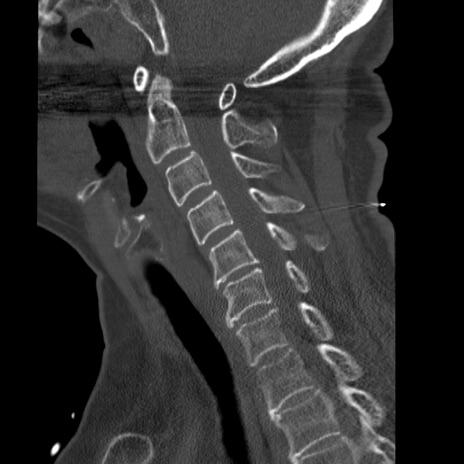

症例50 頚椎CT(矢状断像)

頚椎CT

【症例】60歳代女性

【主訴】後頭部〜右後頸部にかけての痛み

【現病歴】本日飲食店でコーヒーを飲んでいたところ、突然後頭部〜右後頸部にかけて痛みが出現し、右上肢の感覚障害を伴ったため救急要請。

【身体所見】脳神経学的に明らかな異常所見を認めず。右上肢に軽度の感覚障害あり。

異常所見と診断は?